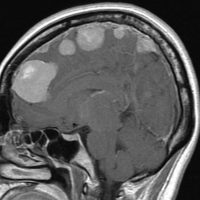

片側髄膜腫症 unilateral meningiomatosis

50歳ころから15年間に3回の開頭手術を受けている患者さんです。parasagittal, falx, convexityなど6個の髄膜腫がすでに摘出されています。左側だけ,テント上だけに髄膜腫が20個くらい多発していました。これらはグレード1で,anaplastic meningiomaの転移ではありません。

やがて蝶形骨縁の髄膜腫の増大速度が早まりatypical meningiomaとなりました。MIB-1 index が10%の高値でした。病理学的にも,psamomatous meningiomaなど様々な種類の髄膜腫が多発しています。

初発時から多発性髄膜腫であり,最初の手術で左側テント上の硬膜を広範囲に摘出しておくべきでした。このような病態は若年者でもみられることがあり,胎生期の硬膜の原基になる細胞にmutationが生じたとしか考えづらいものです。